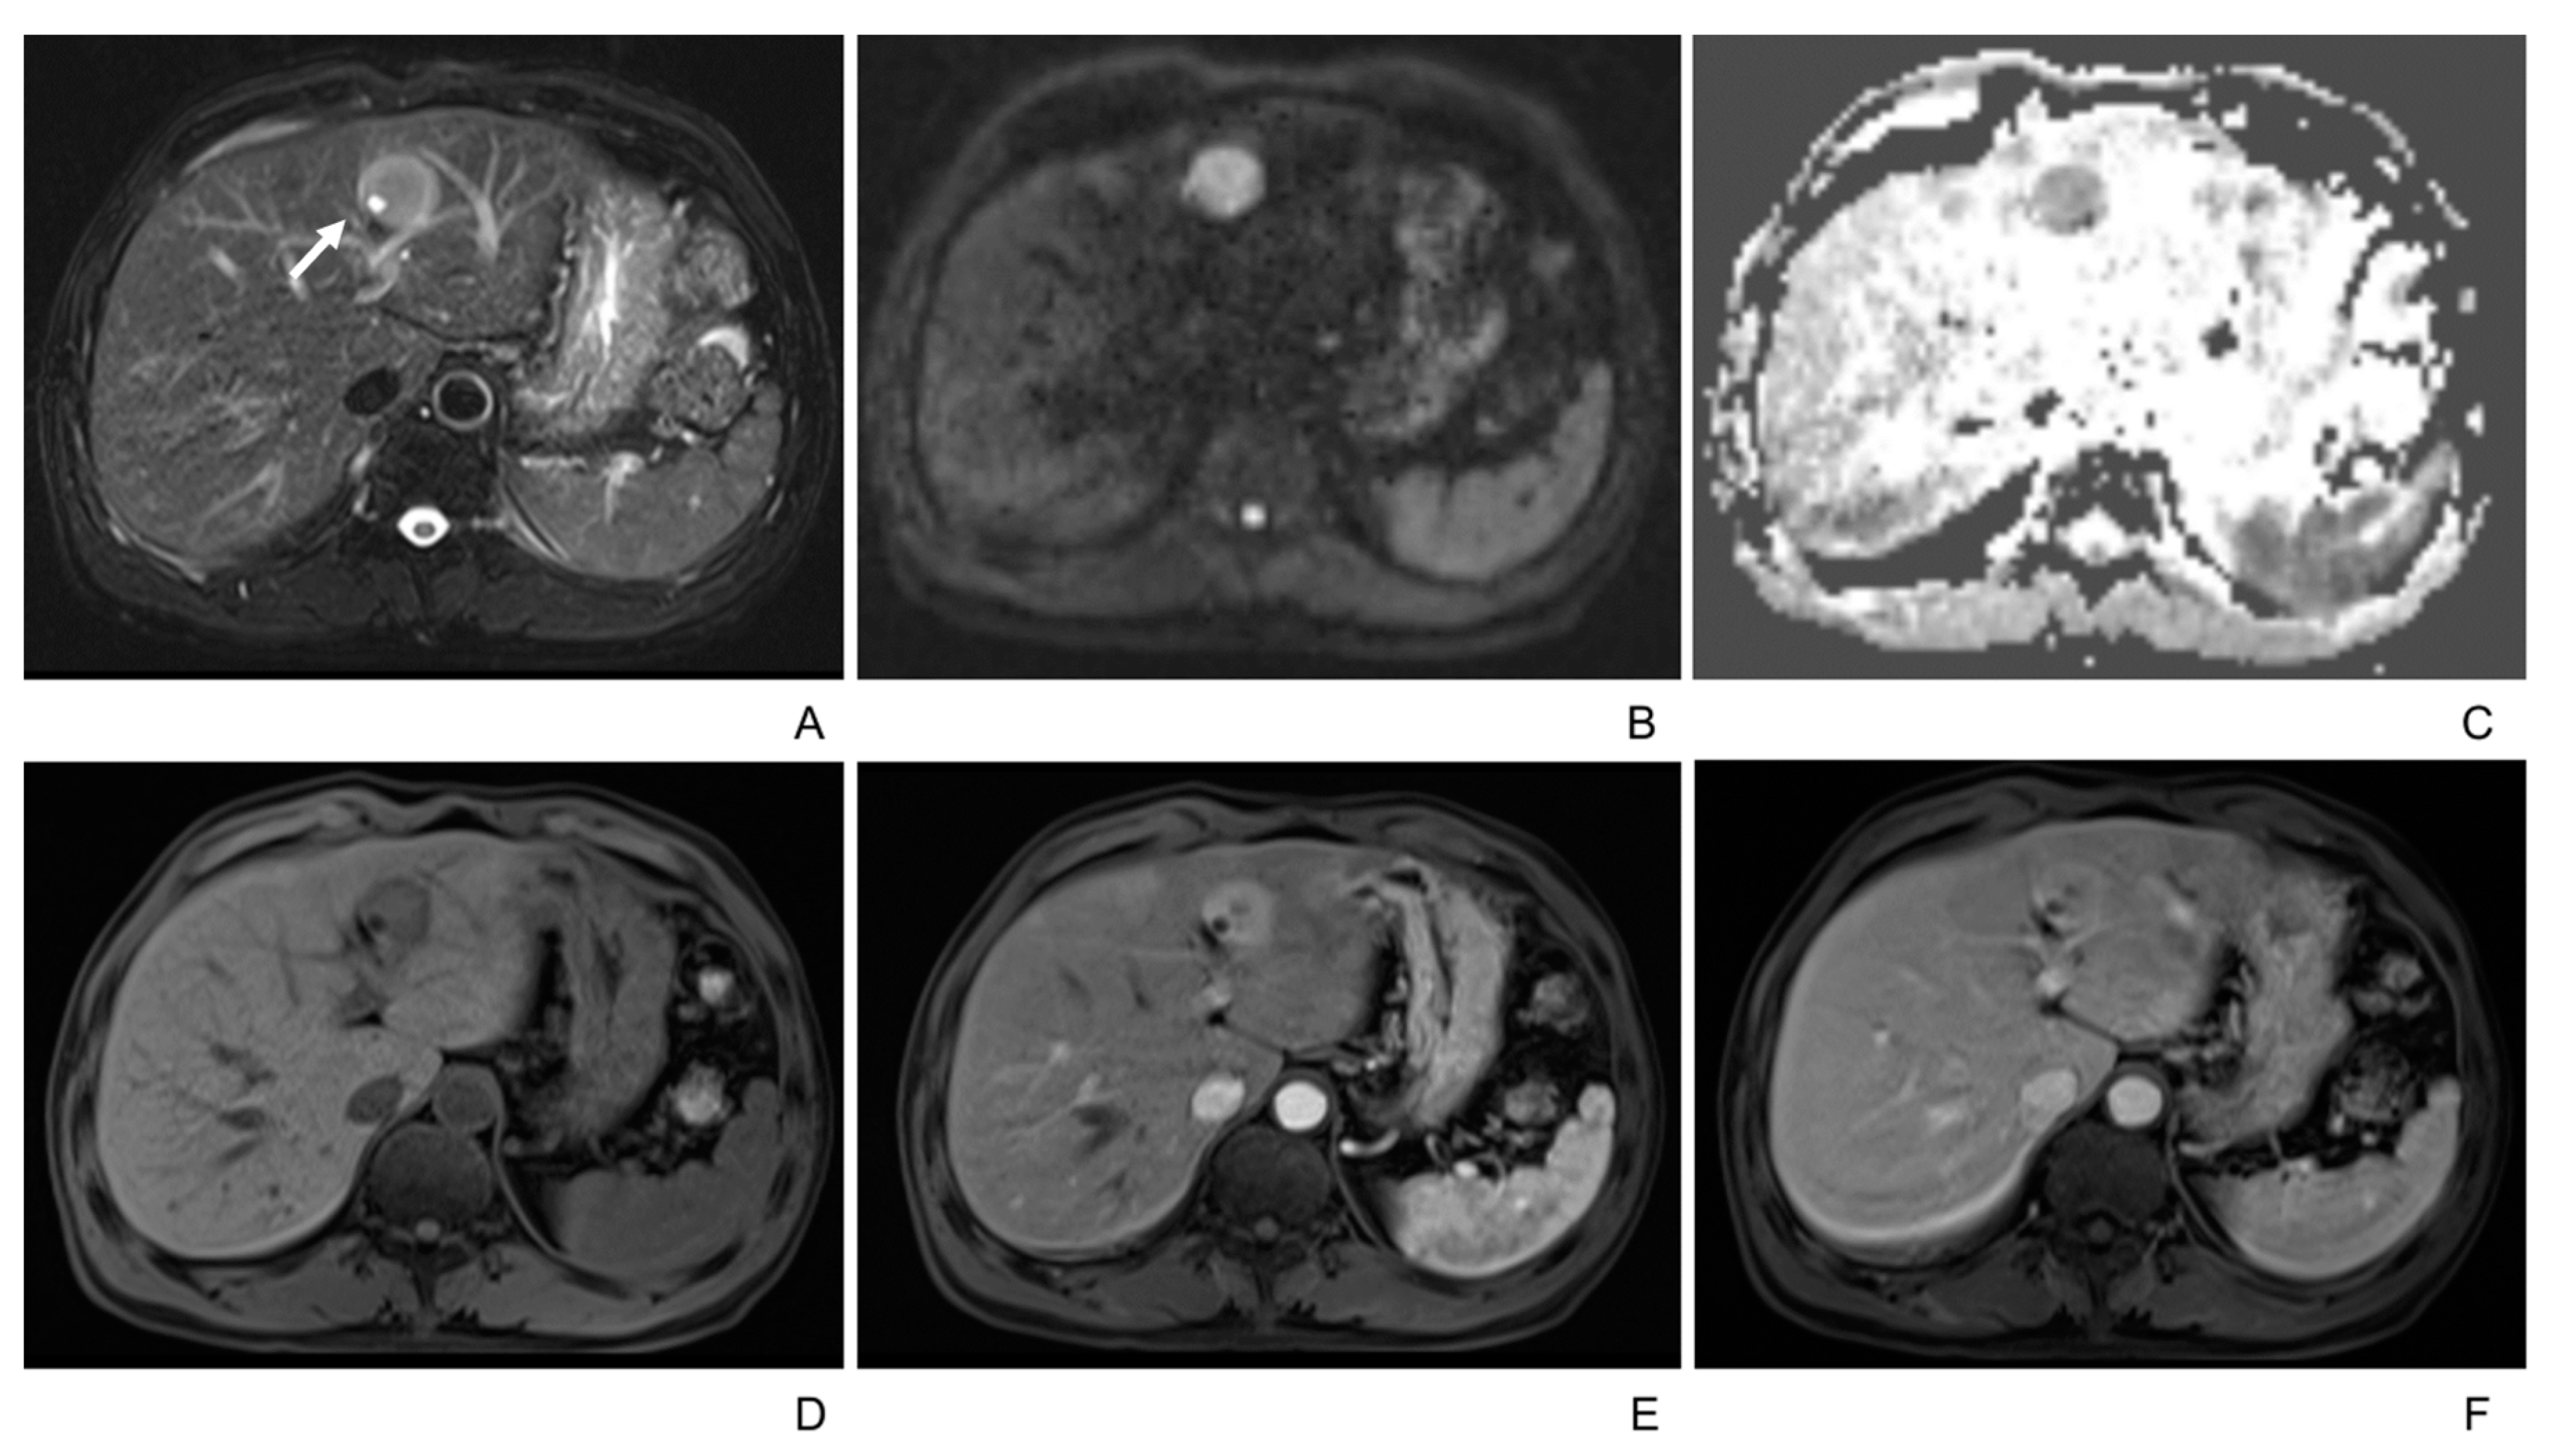

3.2. Imaging Manifestations

- Only two lesions showed a scar-like enhancement in the tumor in AP.

- Two patients underwent the gadoxetic acid-enhanced MRI, and both tumors showed hypointense in the hepatobiliary phase.

| T2WI | |

| Homogenously intermediate/hyperintense | 8 (21%) |

| Peripheral hyperintensity and central hypointensity | 18 (47%) |

| Heterogeneous | 12 (32%) |

| Isointense/not seen | 0 |

| T2 hyperintense foci | 10 (26%) |

| ADC value of lesions (mm2/s) | 1070 ± 255 |

| ADC value of liver (mm2/s) | 1335 ± 351 |

| p = 0.001 (<0.05) | |